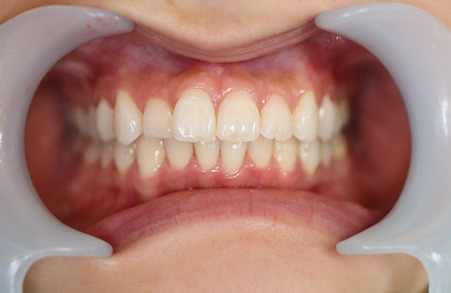

1矯正・マウスピース【治療例1】

治療前

治療後